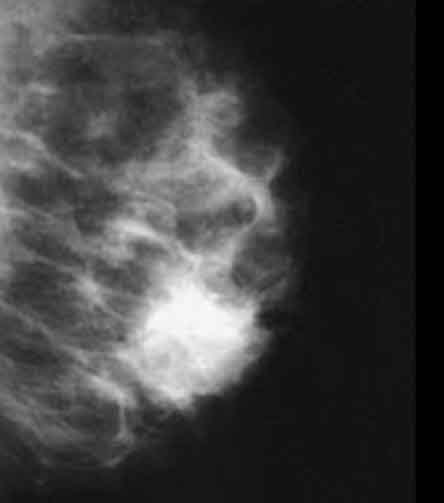

Radiology description

- Mammographically often presents as a spiculated mass with or without calcifications but may present as an architectural distortion or calcifications alone

- Targeted ultrasonography often used to enhance visualization

- MRI often shows enhancing mass lesion with variable washout kinetic patterns (Breast J 2010;16:394)

- MRI is sensitive but nonspecific technique is reserved for screening patients at high risk (e.g., BRCA mutation carriers), patients with dense breast tissue, estimating extent of disease in patients with lobular carcinoma, evaluating response to neoadjuvant chemotherapy or evaluating indeterminate abnormalities on mammography / ultrasound (Breast 2013;22:S77)